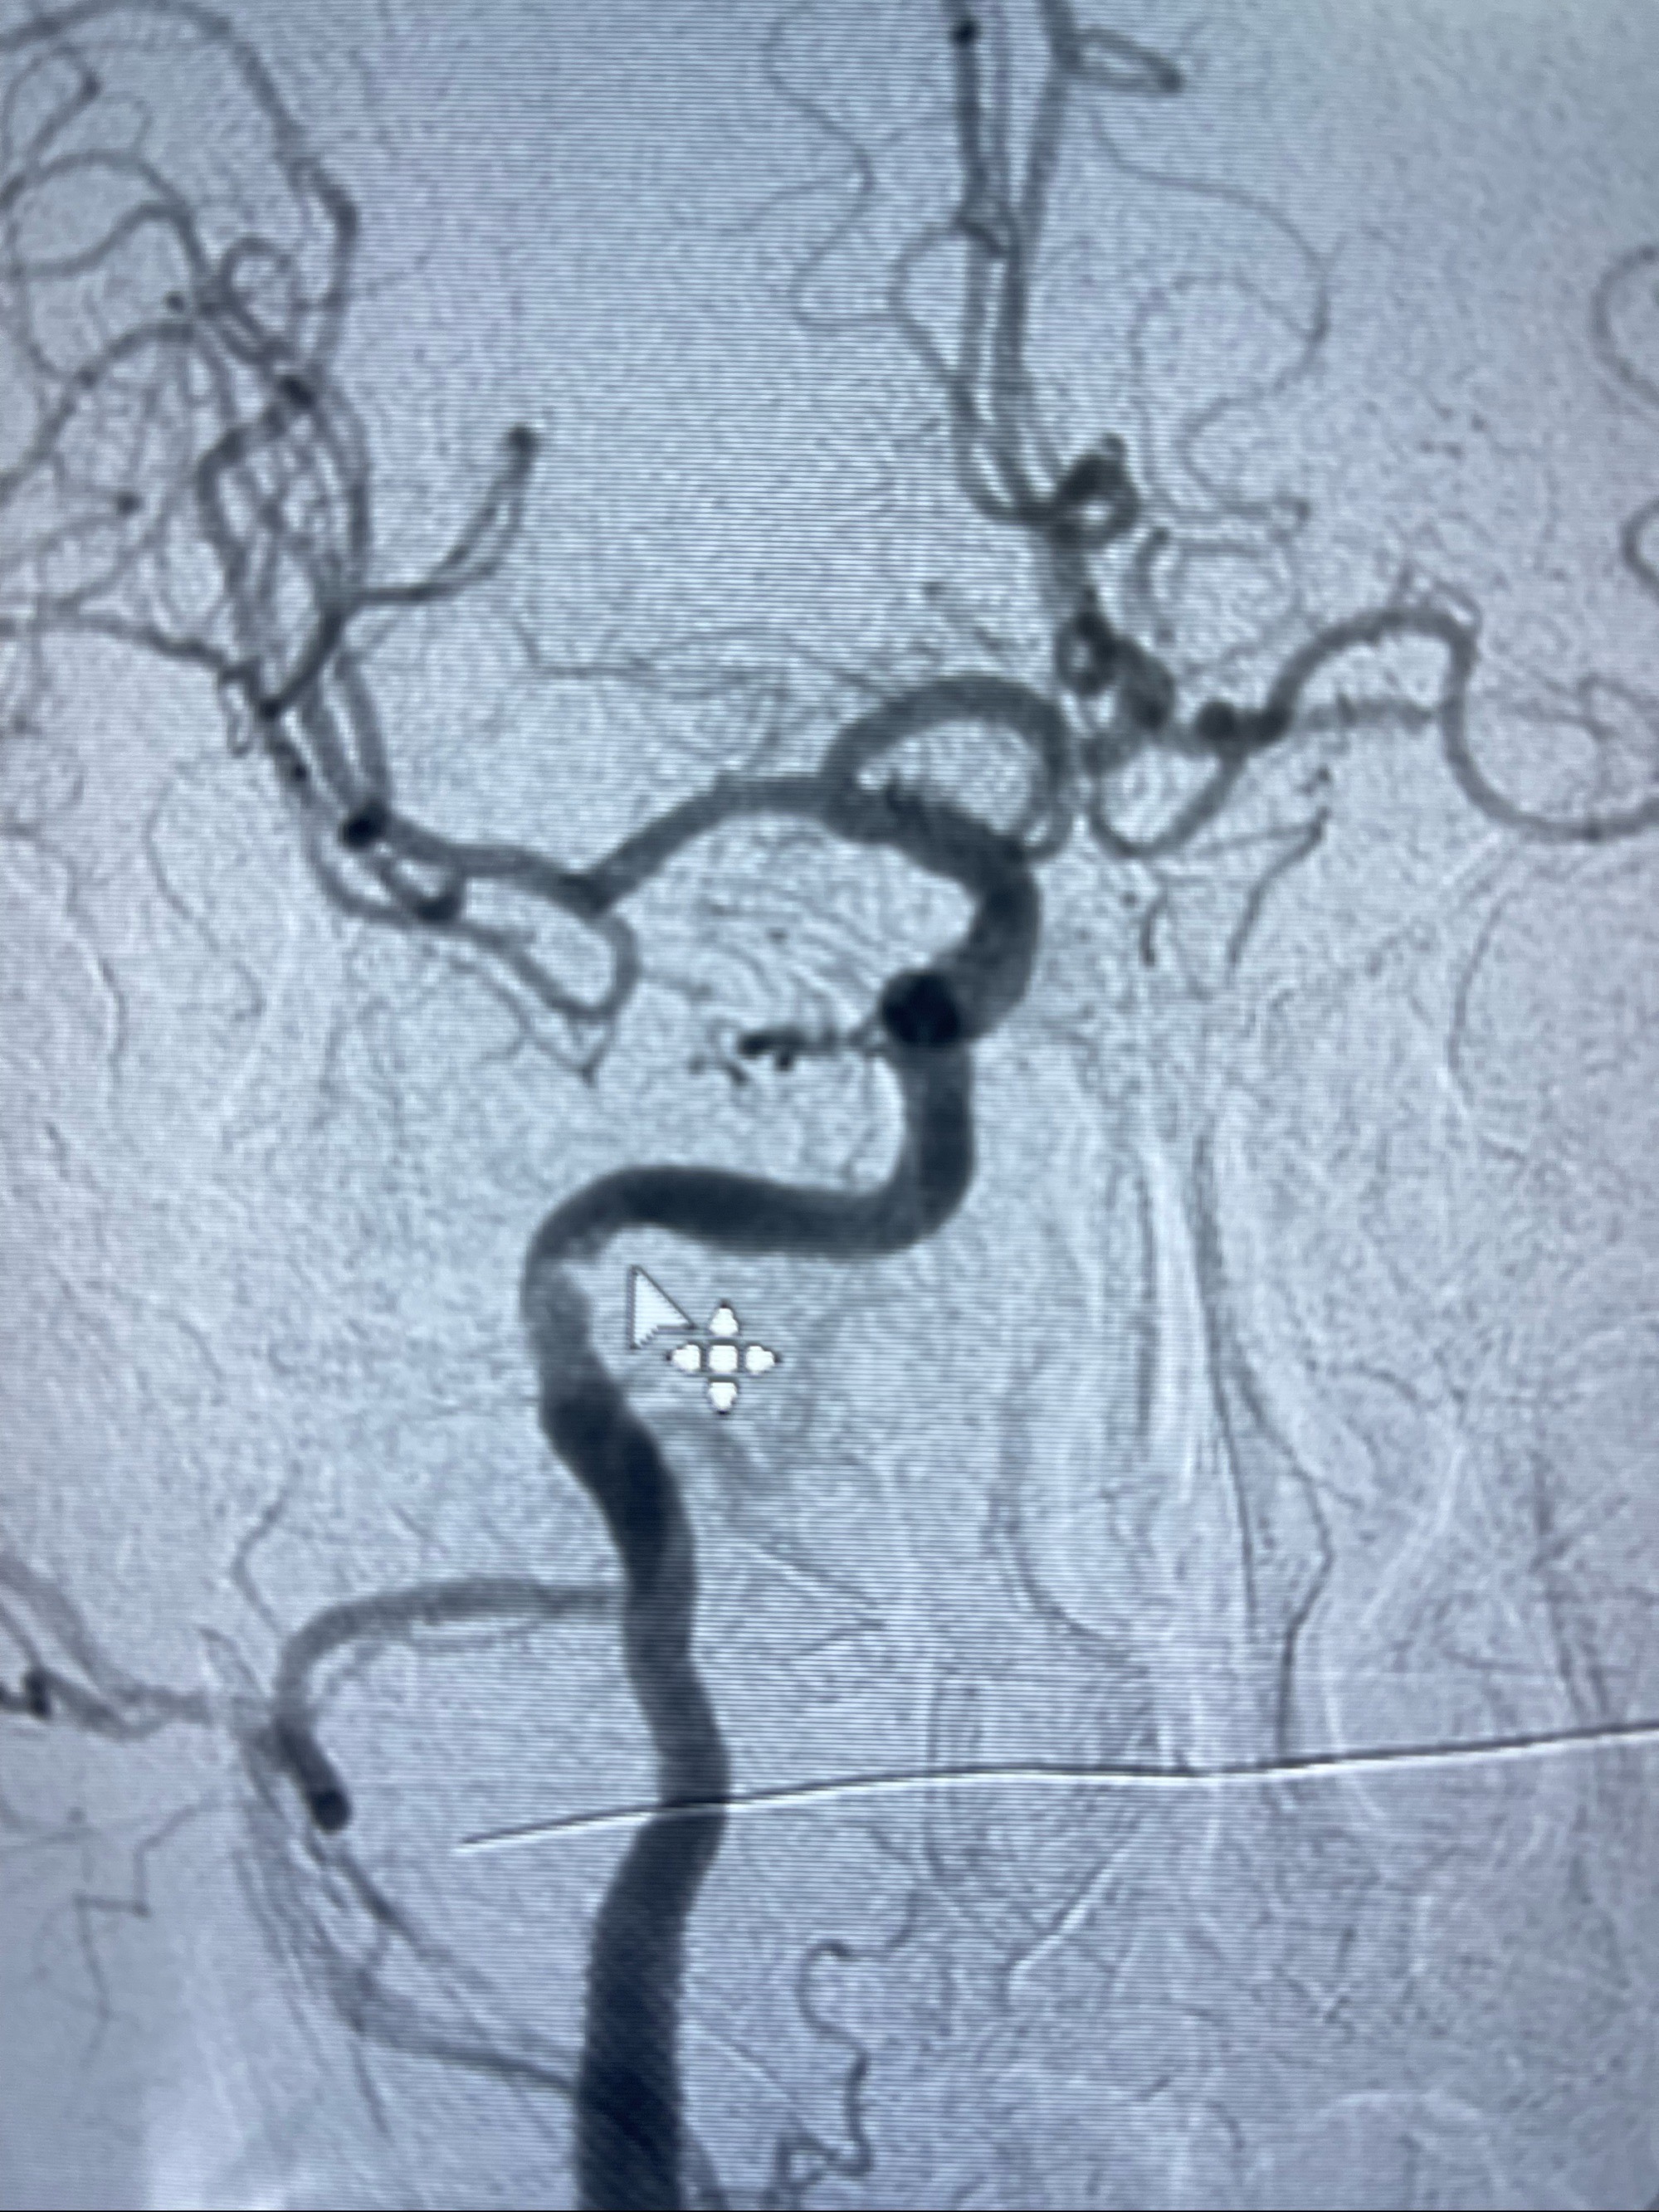

箭头所示为颈内动脉岩骨段重度狭窄,结合MRI,考虑为肿瘤侵犯右侧颈内动脉

路径图下4-20mm球囊在导丝引导下超选择性至狭窄段,以6-8个大气压扩张,持续30s

泄除球囊造影显示局部管腔扩张佳

后移球囊至颈段狭窄段,以8-12个大气压扩张,持续30s后泄除球囊

即刻造影显示狭窄扩张佳

重新行“路径图”,支架导管在微导丝引导下超选择性插入至右侧颈内动脉眼段,4.5-50mmLeo支架释放,远心端位于海绵窦段,近心端位于岩骨段狭窄段以近

即刻造影显示支架贴壁佳

路径图下,5.5-50mmLeo支架导管在微导丝引导下超选择性插入远段Leo支架内

两枚支架部分重叠

多次确认支架位置及打开贴壁情况

支架完全打开,近心端位于原颈动脉支架远心端内